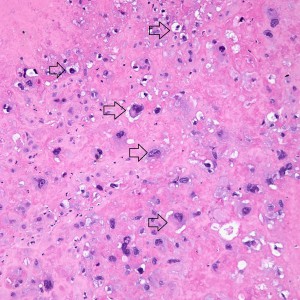

At low power we see throughout the specimen that numerous enlarged hydropic chorionic villi are present (circles).

As we can see, enlarged and hydropic chorionic villi are not especially difficult to find (circle). None of these villi however demonstrate trophoblastic inclusions. There are rare interspersed small chorionic villi (top left) however they are generally rare.

Some villi are so large and hydropic that a few have actually developed central cisterns, spaces within the center of the villi (space highlighted by horizontal lines).

This large hydropic villus with central cistern also demonstrates an important finding: the loss of polarity of the surrounding trophoblasts with circumferential proliferation of variably atypical trophoblastic cells (arrows).